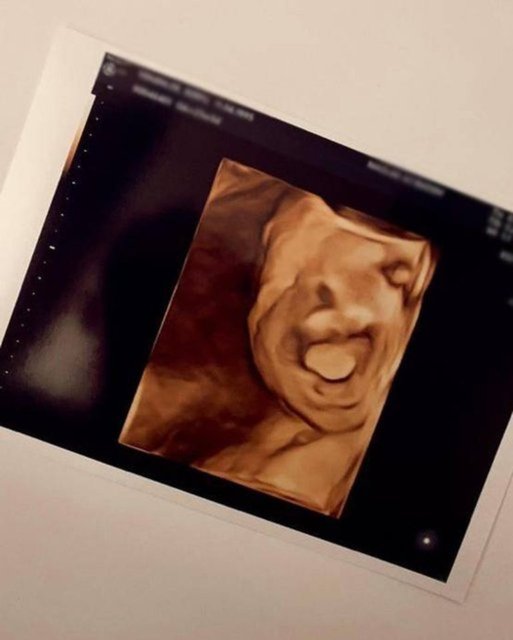

Berfu Yenenler, geçtiğimiz günlerde de bebeğinin ultrason görüntülerini paylaşmıştı.

Yenenler, gönderisine "Ah Mete emmi, güzel yüzünü gösterdi. Burnu yine sana benziyor kocacığım tebrikler. Bu arada sonuncu fotoğrafta gülmüş, siz de gördünüz değil mi?" notunu düşmüştü.